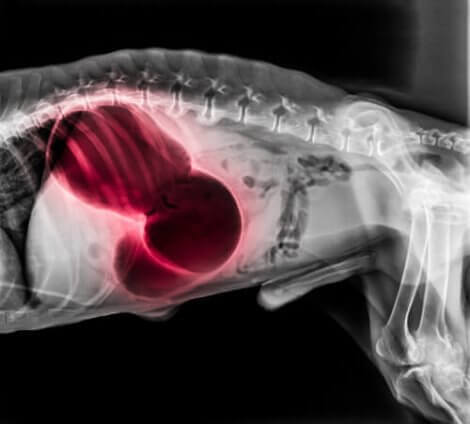

I hjertet eller lungene

En blodpropp i hjertet eller lungene kan gi en rekke alvorlige systemiske symptomer, inkludert besvimelse, kortpustethet og lammelse. Hundens tannkjøtt kan også være blekt eller blått, og det kan hende at de ikke kan sove. Og de kan også begynne å hoste blod. Lungetromboembolisme er vanligvis dødelig.